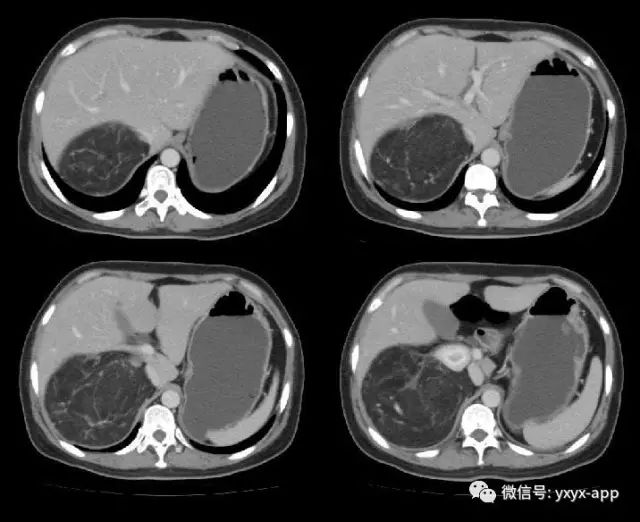

肚肚丫头:右肾中极肾皮质欠完整,呈喇叭口样改变,并可见突出肾脏轮廓的巨大脂肪密度影,其内信号欠均匀,病变边界清楚,周围脏器未见异常密度影及受侵征象,增强扫描病变呈欠均匀较显著强化,腹膜后未见肿大淋巴结。考虑来源于肾脏的含脂肿瘤占位病变,右肾巨大血管平滑肌脂肪瘤可能。鉴别诊断:1. 肾周脂肪肉瘤;2. 腹膜后脂肪瘤/高分化脂肪肉瘤;3. 肾上腺髓质脂肪瘤; 4. 腹膜后畸胎瘤。

【病理结果】肾脏血管平滑肌脂肪瘤

血管平滑肌脂肪瘤是肾脏最常见的良性肿瘤,病理上由平滑肌、脂肪细胞和异常血管混合组成,它们的含量差别较大,多数以脂肪成分为主,少数以平滑肌为主。好发于中年女性,大多数为单侧单发,少数为双侧多发。临床表现主要有肾区疼痛,可有血尿及腹部包块,少数临床上无任何不适症状,体检时偶然发现。

CT 诊断主要根据肿瘤内脂肪成分的显示以及肿瘤内粗大的血管影,由于肾血管平滑肌脂肪瘤含脂肪组织,CT 值在-10~-120HU,增强扫描肿瘤内血管平滑肌组织可明显强化,脂肪组织无强化。由于瘤内血管明显扩张、增厚,缺乏弹力内膜,故常发生肿瘤出血或肾包膜下出血。脂肪成分小于20%的血管平滑肌脂肪瘤影像难以显示脂肪,缺乏特异性的影像表现,不易作出定性诊断,与早期肾癌鉴别困难。